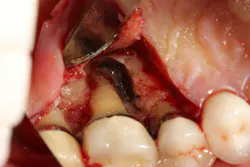

Another advancement in the field of periodontal regenerative medicine has been due to the use of growth factors, proteins, and stem cells. The ability to repair/regenerate a diseased tooth is often dependent upon the extent of the defect, namely the number of bone walls that are left surrounding the tooth. The more bone walls a tooth has left around it (maximum of four), the more blood supply, containment, and space maintenance your graft material will have (figure 5). Bone defects that have three to four walls missing are the hardest to repair and may be slated for extraction (figure 6). By adding growth-stimulating factors to your regular bone grafts (figure 7), an increase in osteopromotive potential occurs that can have the ability to overcome a deficiency of bone walls. (15) Simply stated, your bone graft can become alive, and teeth that were once unable to be repaired now have a chance.

Figure 6: Molar tooth with three walls missing around the palatal root. This tooth would normally be extracted.